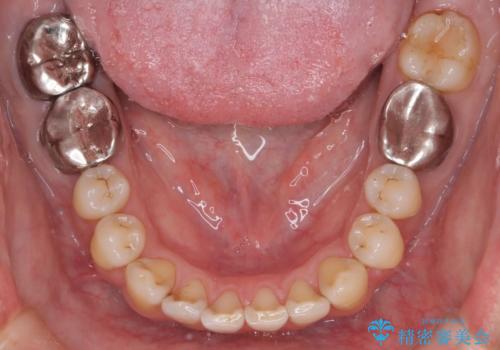

- 前歯の出ているのが気になる、下唇を噛んで痛いとのことで来院された患者様です。マウスピース矯正をご希望でした。

奥歯の噛み合わせはしっかりしていましたので、奥歯の動きは最小限にし、前歯の並びに集中した治療計画+インビザラインのシミュレーションを作成しました。

奥歯の噛み合わせは整っていたため、前歯の並びを美しく修正することに専念できました。マウスピース矯正による治療で短期間で改善しました。